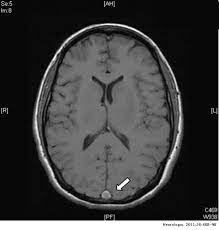

Trombosis venosa con trombocitopenia por la vacuna Ad26.COV2.S COVID-19

03 mayo 2021

Se presentan los primeros casos en Estados Unidos de esta rara complicación asociada a la vacuna para SARS-CoV-2 de los laboratorios Janssen / Johnson & Johnson.  Tal como ocurrió con los casos europeos atribuidos a la vacuna de Oxford/AstraZeneca, las afectadas son mujeres de 18 a 60 años. JAMA, 30 de abril de 2021.